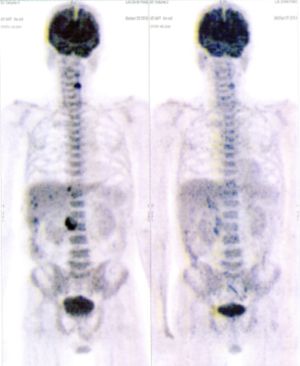

CASE NO: 1 - A FEW MONTHS LATER

A few months after successful treatment for hepatocellular carcinoma, and partially successful for stomach cancer, the PET/CT scan showed the stomach cancer becoming very active, with several metastases to the parts of the liver not previously involved by hepatocellular carcinoma. After a few treatment, all the active stomach cancer lesions in the stomach and in the liver went into remission.